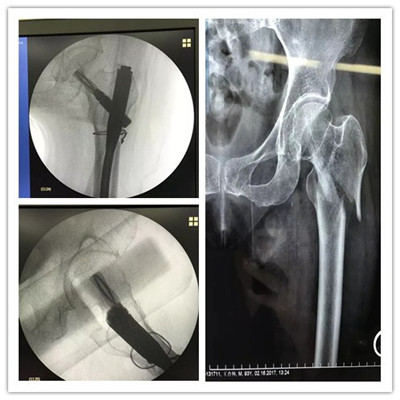

近日,舟山廣安骨傷醫(yī)院成功為一位95歲高齡的老太太實(shí)施股骨粗隆骨折微創(chuàng)手術(shù)。術(shù)后一天就可以床上活動(dòng)。

老太太今年已經(jīng)95歲高齡了,一周前在家不慎滑倒摔傷,疼痛難忍,不敢活動(dòng),遂由家人急送至舟山廣安骨傷醫(yī)院,經(jīng)拍片檢查確診為左股骨粗隆粉碎性骨折。

廣安醫(yī)院關(guān)節(jié)科副主任羅軍稱(chēng),老太太不但高齡,還患有心臟病,低蛋白血癥,重度骨質(zhì)疏松癥,手術(shù)麻醉風(fēng)險(xiǎn)極高,但若保守治療需要長(zhǎng)期臥床,且不說(shuō)骨折能否愈合,致命的臥床并發(fā)癥就極難避免。經(jīng)過(guò)醫(yī)院多科室會(huì)診,在腰部麻醉下,羅軍副主任為老太太實(shí)施了股骨髓內(nèi)釘(PFNA)微創(chuàng)手術(shù)。術(shù)后各項(xiàng)生命體征平穩(wěn),術(shù)后第一天就可床上活動(dòng),目前可以持助行器下地活動(dòng)了。